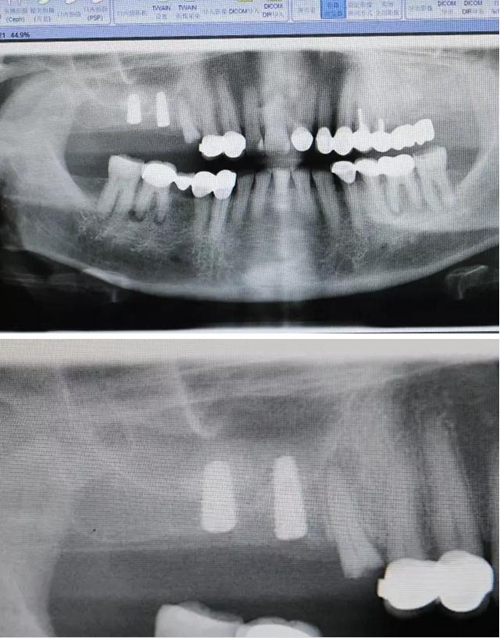

【病例分享】右上內(nèi)提+5冠延長1 梁光強